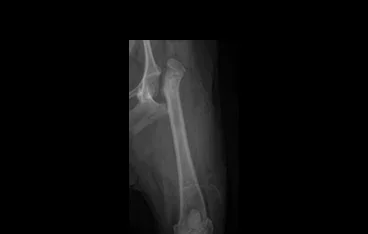

• PLATE

• PLATE 수술 전

PLATE 수술 후